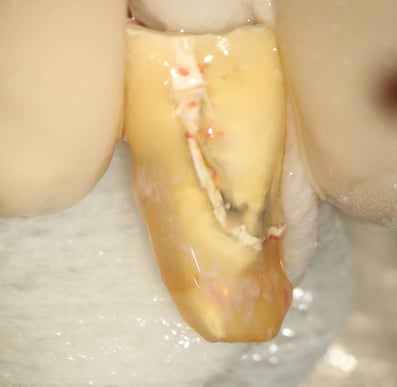

#スプリット 下顎左側第二大臼歯

患者さんの希望により、根管内からの修復を試みたが、経過が思わしくないため、抜歯・再植した症例

#歯根破折